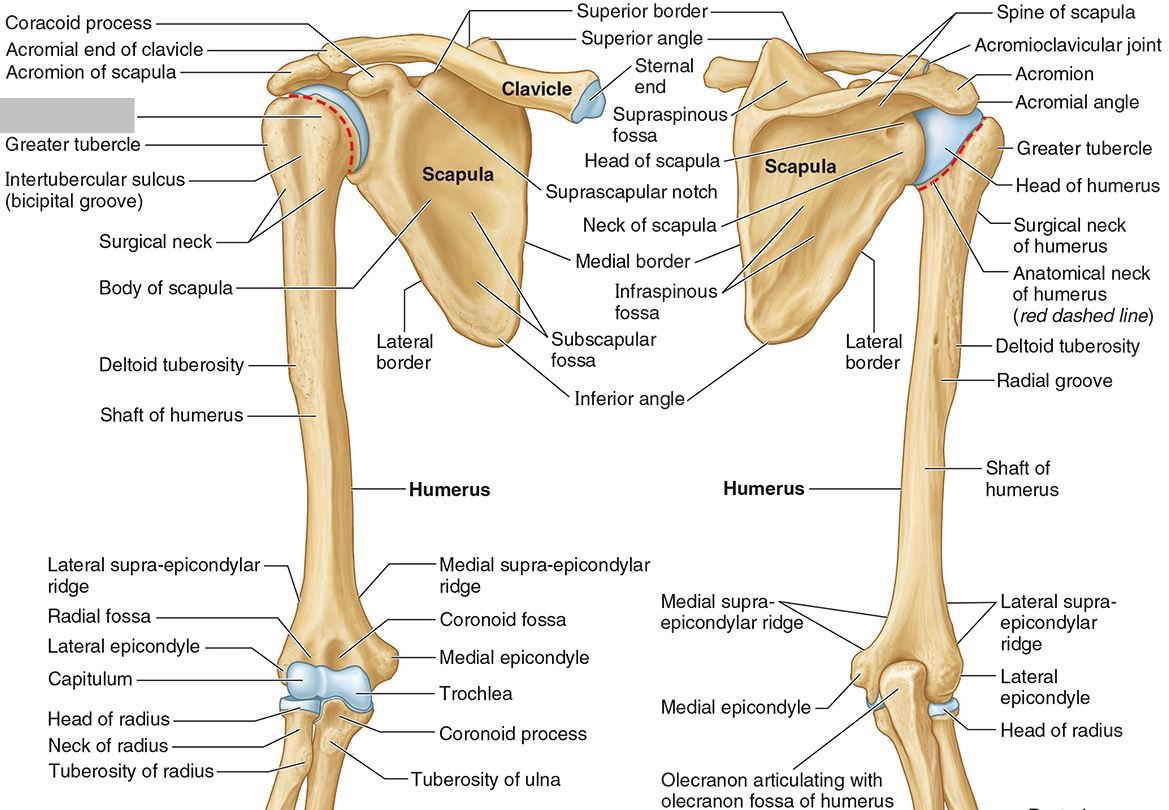

What part of the humerus is this?

The head of the humerus articulates with the scapula at the glenohumeral joint.

What part of the humerus is this?

The anatomic neck is an indentation distal to the head and provides an attachment for the fibrous joint capsule of the glenohumeral joint.

What part of the humerus is this?

The greater tubercle lies lateral and distal to the anatomic neck.

What part of the humerus is this?

The lesser tubercle lies on the anterior/medial side of the humerus, just distal the anatomic neck.

What part of the humerus is this?

The intertubercular (bicipital) groove lies between the greater and lesser tubercles.

What part of the humerus is this?

The surgical neck is a narrow area distal to the tubercles. It is a common site for proximal humerus fractures.

What part of the humerus is this?

The humeral shaft features the deltoid tuberosity laterally for the distal insertion of the deltoid muscle.

What part of the humerus is this?

The radial groove is an oblique depression that contains the radial nerve and deep brachial artery.

Which parts of the humerus is this?

The medial and lateral epicondyles are distal prominences to which many forearm tendons attach, near the elbow joint.

Which parts of the humerus is this?

The medial and lateral supracondylar ridges extend superiorly from the medial and lateral epicondyles.

Which parts of the humerus is this?

The trochlea and the capitulum (the condyles) are the most distal surfaces of the humerus, where it articulates with the forearm bones at the elbow joint

What part of the humerus is this?

The olecranon fossa is a posterior depression above the trochlea that receives that olecranon process of the ulna

What part of the humerus is this?

The coronoid fossa is an anterior depression above the trochlea that receives that coronoid process of the ulna.